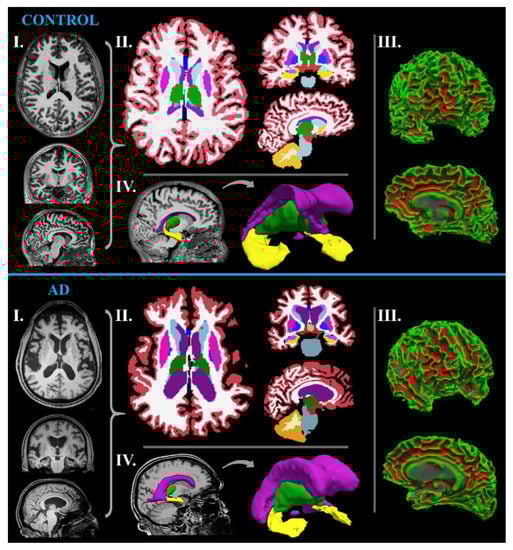

MR-Volumetry

- Chandra, A.; Dervenoulas, G.; Politis, M.; Alzheimer’s Disease Neuroimaging, I. Magnetic resonance imaging in Alzheimer’s disease and mild cognitive impairment. J. Neurol. 2019, 266, 1293–1302. [Google Scholar] [CrossRef] [PubMed]

- Desikan, R.S.; Cabral, H.J.; Hess, C.P.; Dillon, W.P.; Glastonbury, C.M.; Weiner, M.W.; Schmansky, N.J.; Greve, D.N.; Salat, D.H.; Buckner, R.L.; et al. Automated MRI measures identify individuals with mild cognitive impairment and Alzheimer’s disease. Brain 2009, 132, 2048–2057. [Google Scholar] [CrossRef]

| MR-volumetry | sensitive tissue volume changes | several non-standardized softwares |